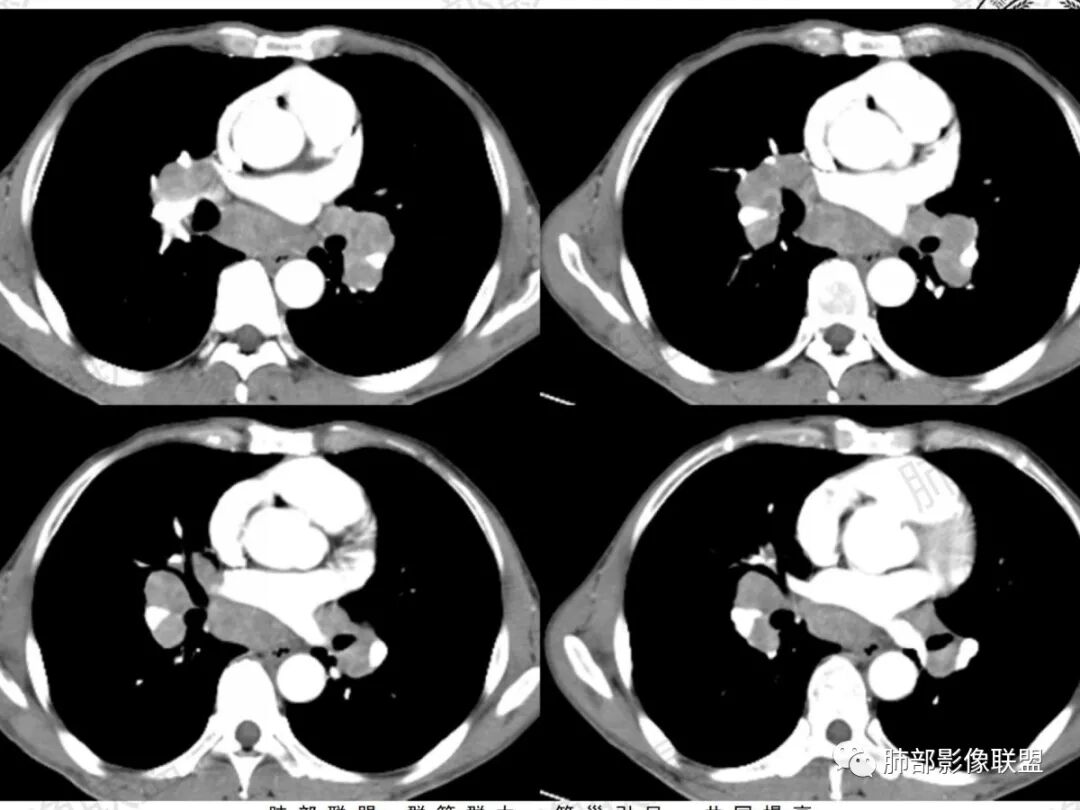

中年男性,干咳、淋巴结肿大,双肺支气管血管束周围多发细小结节影,纵隔、肺门淋巴结增大,增强淋巴结强化不明显,未见明显环形强化,考虑结节病,鉴别结核,淋巴瘤。

双肺弥漫性粟粒样结节,病史有粉尘工作,可能尘肺,纵隔、肺门淋巴结肿大,部分融合包绕血管,边缘清楚,内部密度欠均匀,腹部也可见类圆形淋巴结,内部可见坏死,环形强化,考虑:结节病,鉴别:淋巴瘤,小细胞肺癌,结核。

老年男性病人,肺门纵隔淋巴结肿大,具有弥漫性及融合性的特点,肺内有散在多发的微小结节病变,腹主动脉旁淋巴结肿大。第一印象考虑结节病,鉴别诊断淋巴瘤。

中年男性,双肺野多发粟粒样结节影,纵隔及肺门多发肿大淋巴结,内有坏死,边界不清,轻度强化,对称分布,考虑结节病可能性大,鉴别肺结核。

中年男性患者,反复干嗽半年,近期咳嗽有痰,胸部CT示:双侧肺门及纵隔淋巴结肿大,呈对称性,有融合趋势,部分淋巴结内有坏死,肺内散在小结节,常规考虑结节病,但结节病淋巴结一般边界清晰,少见融合,本例患者不能排除恶性(淋巴瘤,小细胞,转移)和结核,进一步淋巴结活检予以明确。

中年男性,干咳半年。双侧肺门纵隔对称性淋巴结肿大,大部分肿大的淋巴结与周围血管之间的脂肪间隙消失,部分有融合坏死,无钙化;肺内多发小结节,右侧叶裂多发结节,腹膜后淋巴结肿大并坏死。考虑纵隔及肺门肿大淋巴结考虑为转移可能性大,鉴别结节病(淋巴多不融合、可见钙化)、结核(可融合、环形薄壁强化)。

双肺门及纵隔对称性淋巴结肿大,有融合坏死,肺内多发粟粒结节,叶间裂也有,右肺上叶前段亚段支气管狭窄,腔内密度增高;腹膜后淋巴结肿大坏死,老年男性,4月外院没提淋巴结,考虑结核,鉴别淋巴瘤,转移瘤,结节病,鳞癌

纵隔及双肺门肿大淋巴结,病灶似乎有融合,但是好像比较独立

这里好像有融合

密度较均匀,强化比较明显,有一些地方有些稍低密度。

两肺弥漫细小结节,考虑血道吧

结节病累及肺部表现:肺内多发结节,主要沿血管束、淋巴管周、小叶间隔、胸膜下分布,可呈串珠样改变。结节较大时可以融合;还可有实变及团块影;后期纤维化不可逆。

结节病的肺门及纵隔淋巴结增大也较有特点,较少融合,较坚硬密实,密度偏高,可钙化。偶或可以观察到低密度坏死,但较少且轻微。